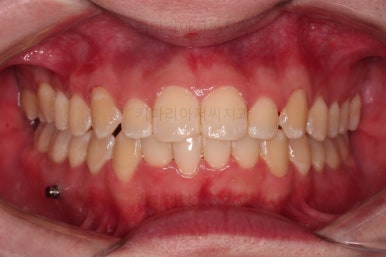

이제 전후 비교를 해볼게요.

1년 7개월 만에 매우 고난이도의 치료를 임플란트 없이 사랑니까지 당겨와서 사용한 만족스러운 치료였습니다.

하지만 임플란트 없이 충분히 가능할 수 있게끔 해주어서 환자분도 매우 만족하는 치료가 되었어요.

뿌리도 남아있었고 골 결손도 심했던터라 뒤쪽 치아들이 잘 움직일 것을 고지해 드렸었지만 다행히 거의 문제 없이 치아가 잘 움직였고요.

대신 해당 치아는 뼈가 약하다는 걸 환자분도 인지하시고 관리를 잘해야되는 부분입니다.